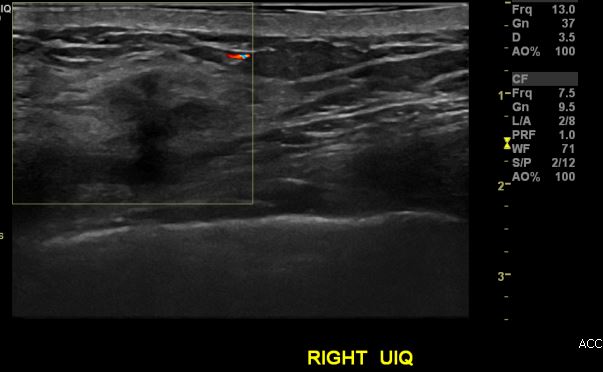

상기환자 건강검진상 이상소견으로 내원하신 50대 여성분으로 우측 유방 상외사분면에

의심스러운 멍울 조직검사 시행하여 우측 침윤성 유관암 진단되었습니다.